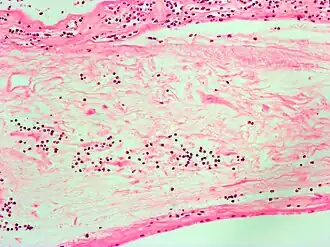

| Micrografia mostrando corioamnionite. Coloração H&E. | |

Corioamnionite é uma inflamação das membranas fetais (âmnio e córion), do liquido amniótico, placenta e/ou decíduas devido a uma infecção bacteriana. Tem mostrado-se de prevalência variável nos estudos, podendo acometer até 10% das gestações e até 40% dos casos de síndromes febris no trabalho de parto.[1] Geralmente resulta devido a bactérias que migraram ao útero através da vagina e está frequentemente associado a um trabalho de parto prolongado.